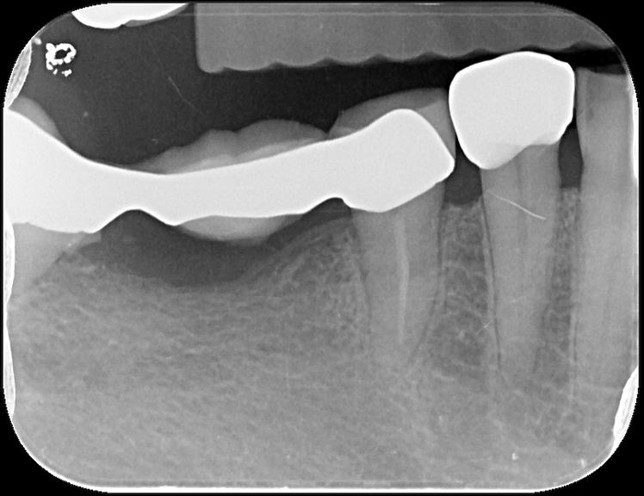

治療後,牙齦反應良好

治療後,假牙邊緣密合度理想

術前、術後比較